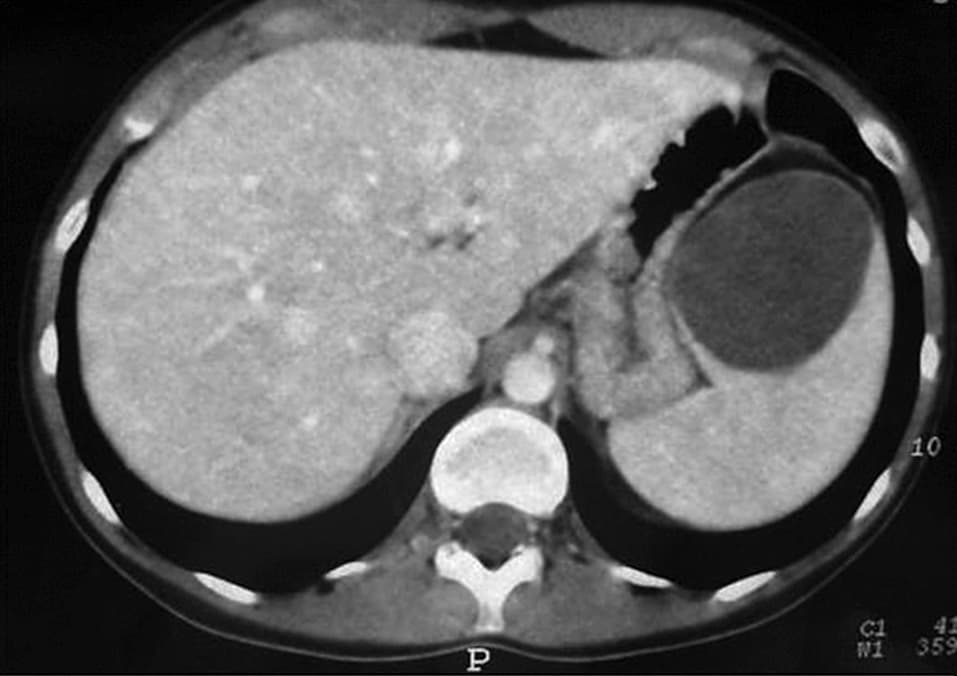

TROMBOSIS ESPLÉNICA

INFARTO ESPLÉNICO

QUISTES ESPLÉNICOS